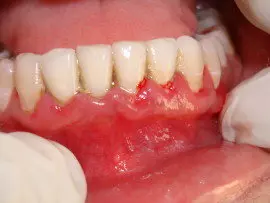

Treatment of Pyorrhea includes cleaning of teeth, Periodontal Flap Surgeries & Other Advanced Procedures Like Bone Grafting & Guided Tissue Regeneration [GTR]

In addition, Periodontist Ahmedabad Dr. Viral Patel treats gum disease and tooth decay(periodontal disease) with variety of dental treatments like scaling or cleaning of teeth, deep cleaning, periodontal flap surgery [gum surgery], laser assisted periodontal therapy, bone grafting procedures, guided tissue regeneration [GTR] & more latest modalities like concentrated growth factors & dental stem cell procedures.